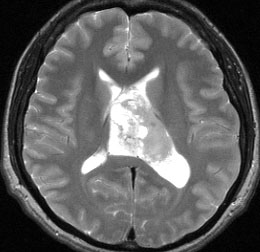

無症状の若い女性に偶然発見された例

central neurocytomaは腫瘍実質部分が多いものです。しかし,この例のように腫瘍の大部分をのう胞が占める症例もあります。

anterior transcallosal apprroachで亜全摘出しました。20代の女性でしたが,その後,子どもも生まれて元気です。

腫瘍の位置から,透明中核が発生母地であることが推測されます。central neurocytomaは,惻脳室壁にべとべとくっつくので,脳質上衣からの剥離は簡単ではありません。鑑別しなければならないのが,成人の毛様細胞性星細胞腫ですが,この症例では決定的な鑑別点はないでしょう。のう胞性の毛様細胞性星細胞腫と同様に,腫瘍の増殖力は低く無理して全摘出するものではありません。